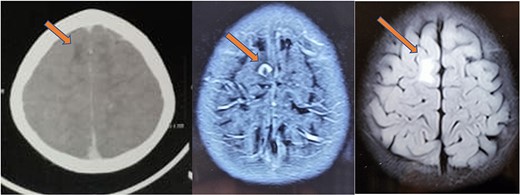

The histopathology report revealed the presence of a parasite composed of cuticle, subcuticular cells along with muscle, and chronic inflammatory infiltrate with a final impression of cysticercosis (Fig. 5). After this diagnosis, we reevaluated our history with more details. There was no history of headaches, seizures, or visual difficulties. The patient was found to be a vegetarian in diet. A pediatric physician evaluation was also done where a contrast-enhanced computed tomography (CECT) brain and ophthalmic examination were advised to evaluate for a possibility of neurocysticercosis. The ophthalmic examination was within normal limits, but the CECT showed a hypodense area in the right frontal lobe (Fig. 6). On further correlation with contrast MRI, a ring-enhancing lesion in the right paramedian frontal lobe surrounded by non-enhancing vasogenic edema was seen. Another small lesion was seen in the right external capsule surrounded by minimal edema (Fig. 6). Both lesions appeared to be granulomatous, giving an impression of neurocysticercosis. The child was treated with syrup albendazole 15 mg/kg per day in two divided doses for 1 month. A short course cover of dexamethasone 0.1 mg/kg per day started 1 day before albendazole was started, continued for a month, and then tapered over a week.

CT (left) showing a hypodense lesion in the right frontal lobe, T1 post-contrast MRI image (center) showing a ring enhancing lesion in the right frontal lobe and FLAIR image (right) showing non-enhancing vasogenic edema surrounding the lesion.

At 1-month follow-up, the patient had complete resolution of pain and swelling. Local USG back showed no evidence of any remnant lesion. At the 6-month follow-up, an MRI of the brain was done that showed a major reduction in the size of the lesion and resolution of perilesional edema (Fig. 7). At 1-year follow-up, the patient was found to be completely symptom-free, managing his activities of daily life, very well.

Repeat MRI at 6 months showing resolved changes with reduction in size of the lesion with resolution of perilesional edema.